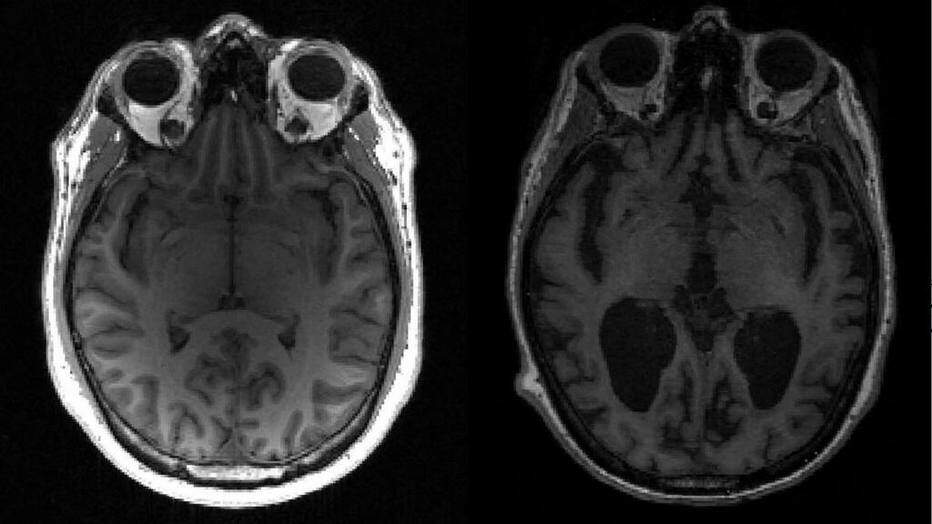

No Alzheimer, a tau e outra proteína chamada beta amilóide se acumulam em nós e placas – ambas conhecidas como agregados – que matam as células cerebrais e encolhem o cérebro. Isso, por sua vez, resulta em perda de memória, alterações de personalidade e incapacidade de realizar funções cotidianas. Estima-se que 44 milhões de pessoas sofram da doença em todo o mundo.

O grau da doença de Alzheimer é medido de acordo com a chamada “Escala de Braak”. A equipe descobriu que leva cerca de 35 anos para progredir do estágio três, quando os sintomas leves começam a aparecer, para o estágio seis, o mais avançado.

Se os agregados dobram aproximadamente em cinco anos, em 35 anos eles teriam se multiplicado por 128. Esse crescimento exponencial “explica por que a doença demora tanto para se desenvolver e então a pessoa se deteriora rapidamente”.